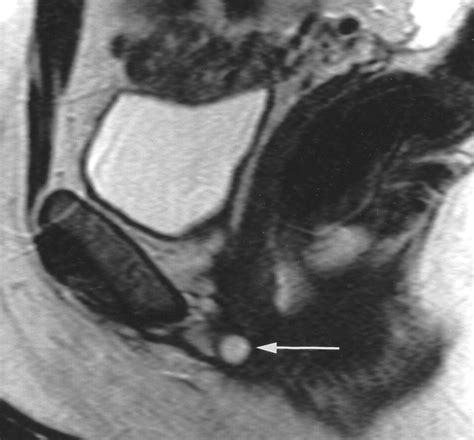

• Imaging Tests: Ultrasound or magnetic resonance imaging (MRI) may be used to confirm the diagnosis and determine the size and location of the cyst.

• skene duct cyst radiopaedia

• skene gland cyst